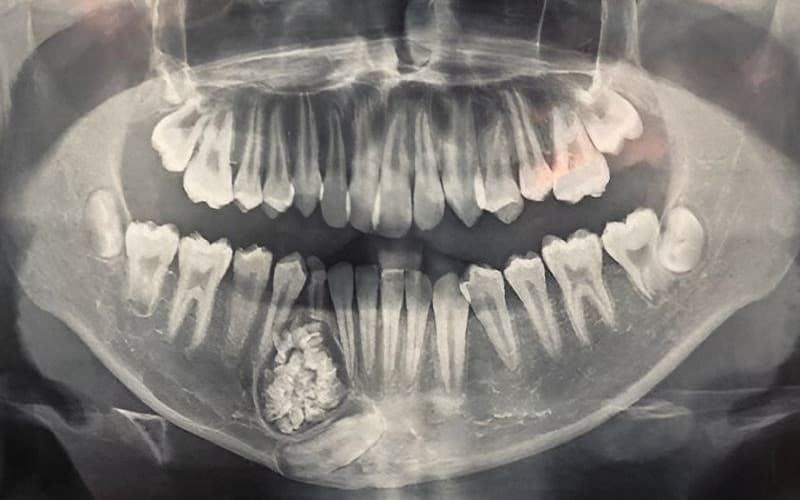

Do đặc điểm dễ tái phát, bệnh nhân cần được theo dõi lâu dài, thậm chí 5 – 10 năm hoặc hơn. Nên chụp phim Panorama (X-quang toàn cảnh hàm mặt) định kỳ khoảng 6 tháng/ lần trong giai đoạn đầu, sau đó giãn khoảng cách theo chỉ định bác sĩ nếu ổn định. Khi nghi ngờ tái phát hoặc tổn thương lan rộng, có thể cần chụp CT để đánh giá chi tiết hơn. Việc tái khám và chụp phim định kỳ giúp phát hiện sớm bất thường, xử lý kịp thời trước khi tổn thương lan rộng hoặc gây phá hủy xương nghiêm trọng.